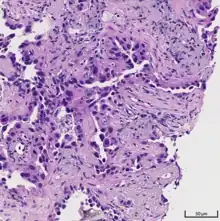

| A gross pathological specimen of a pulmonary adenocarcinoma, removed in a lobectomy. | |

Adenocarcinoma of the lung tends to stain mucin positive as it is derived from the mucus-producing glands of the lungs. Similar to other adenocarcinoma, if this tumor is well differentiated (low grade) it will resemble the normal glandular structure. Poorly differentiated adenocarcinoma will not resemble the normal glands (high grade) and will be detected by seeing that they stain positive for mucin (which the glands produce). Adenocarcinoma can also be distinguished by staining for TTF-1, a cell marker for adenocarcinoma.[29]

As discussed previously, the category of adenocarcinoma includes are range of subtypes, and any one tumor tends to be heterogeneous in composition. Several major subtypes are currently recognized by the World Health Organization (WHO)[1] and the International Association for the Study of Lung Cancer (IASLC) / American Thoracic Society (ATS) / European Respiratory Society (ERS):[30][31][32] lepidic predominant adenocarcinoma, acinar predominant adenocarcinoma, papillary predominant adenocarcinoma, micropapillary predominant adenocarcinoma, solid predominant adenocarcinoma, and solid predominant with mucin production. In as many as 80% of these tumors, components of more than one subtype will be recognized. Surgically resected tumors should be classified by comprehensive histological subtyping, describing patterns of involvement in increments of 5%. The predominant histologic subtype is then used to classify the tumor overall.[2] The predominant subtype is prognostic for survival after complete resection.[33]

To reveal the adenocarcinomatous lineage of the solid variant, demonstration of intracellular mucin production may be performed. Foci of squamous metaplasia and dysplasia may be present in the epithelium proximal to adenocarcinomas, but these are not the precursor lesions for this tumor. Rather, the precursor of peripheral adenocarcinomas has been termed atypical adenomatous hyperplasia (AAH).[10] Microscopically, AAH is a well-demarcated focus of epithelial proliferation, containing cuboidal to low-columnar cells resembling club cells or type II pneumocytes.[10] These demonstrate various degrees of cytologic atypia, including hyperchromasia, pleomorphism, prominent nucleoli.[10] However, the atypia is not to the extent as seen in frank adenocarcinomas.[10] Lesions of AAH are monoclonal, and they share many of the molecular aberrations (like KRAS mutations) that are associated with adenocarcinomas.[10]